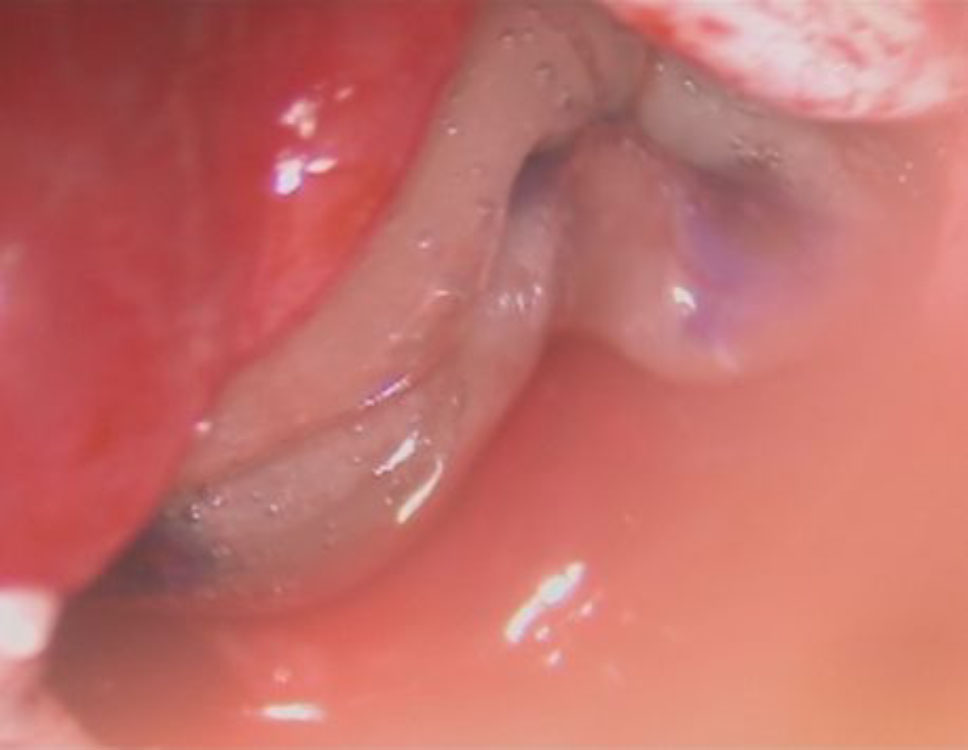

術中写真

摘出 前

摘出 中

摘出 後